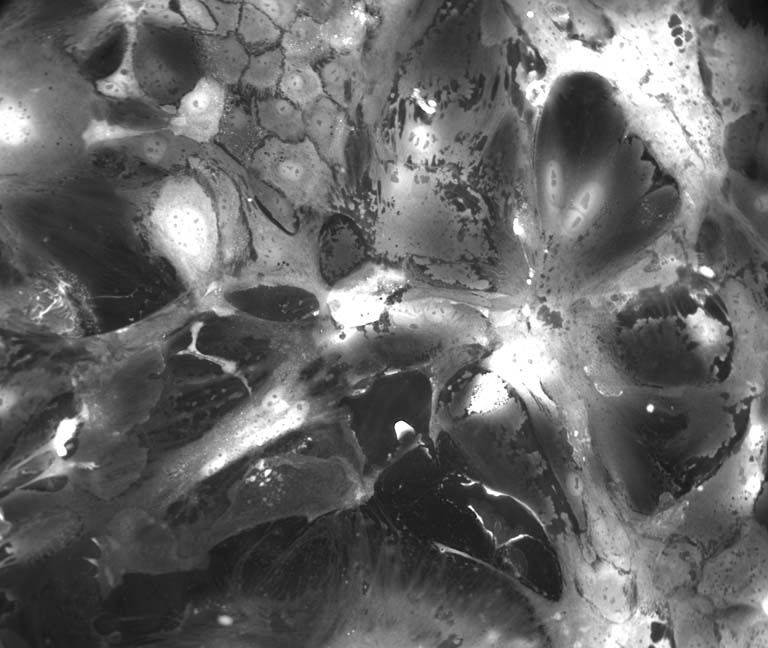

These images show cancer cells in the process of adapting to a new growth format, which will enable us to understand how cancer cells alter their metabolic behavior to survive in different environments. These images were of cancer cells that had been grown in 3D matrices previously and were transferred to a 2D growth format where they exhibit dramatic alterations and a high degree of variability, which we were documenting.

In this project we are trying to understand whether the growth format, nutrient conditions, or which mutations the cancer cells have is the most important variable for determining their metabolic behavior. These images are of one of the genotypes (APC-/- ; KRASG12D ; p53-/-) grown in a 2D format, and represents 1 of 32 conditions we are systematically profiling.